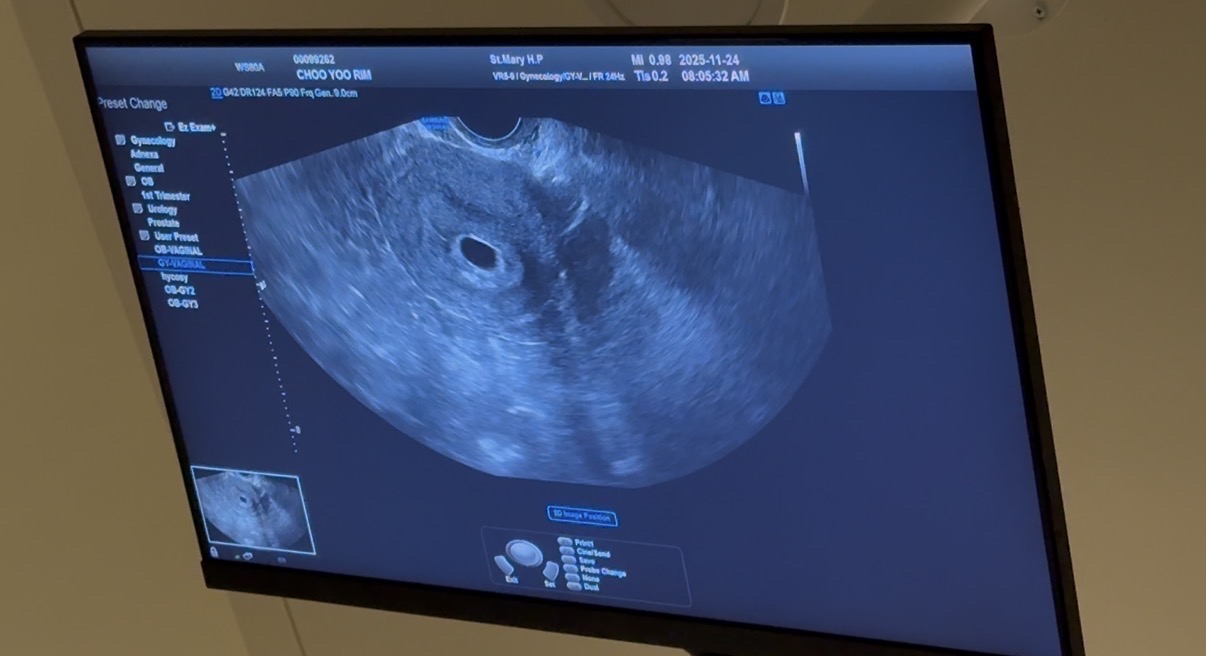

생리시작일은 10/7일 배란이 좀 늦었고 10/24-25일 배란 추정(25일 배란됨 확인) 11/08일 첫 두줄 확인 11/15일 아기집 0.33cm (아기집이 너무 작다하시면서 4주5일로 진단) 11/24 아기집 재방문, 아기집은 커졌으나 난황과 아기가 안보인다고 하심, 11/27일 재방문 예정 너무 마음이 복잡하네요ㅠㅠ 수원에 초음파 잘 보는 곳 아시는분 계실까요..!